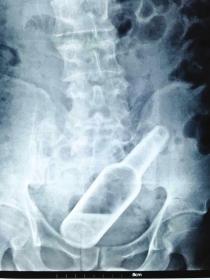

《长株潭报》株洲讯(记者杜方江通讯员梁辉)欠债没还,*债追**人恼羞成怒操起玻璃瓶从肛门处塞入长沙男子李钱缺(化名)体内。9月1日凌晨,他赶到湖南省人民医院急诊科就医。

50来岁的李钱缺离异多年。8月30日,他被*债追**人从肛门强行塞入一个装花露水的玻璃瓶。从B超和CT上可清晰看到,玻璃瓶底朝下嵌在李钱缺的直肠下段,瓶内还有小半瓶液体。结直肠肛门外科医生董宏宇表示,因异物进入体内已有2天,已造成肛门括约肌损伤和肠壁严重水肿,只能通过开腹手术将异物取出。

“我们曾经收治过塞玻璃杯、手电筒的。”董宏宇提醒,肛门被塞进异物后一定要及时就医,否则导致肠破裂大出血,将危及生命。